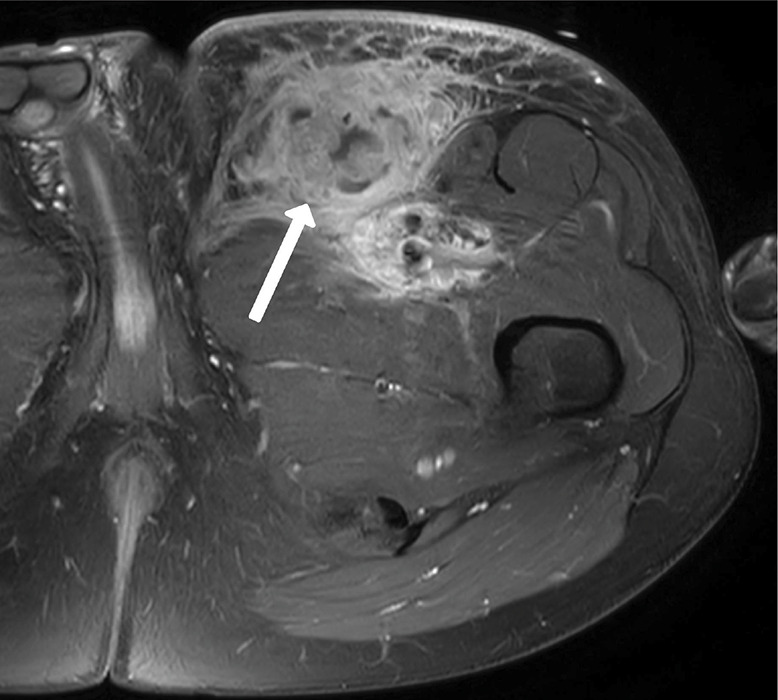

教学点:卡波西肉瘤是一种罕见的疾病,最常见于人类免疫缺陷病毒(HIV)患者、接受免疫抑制剂的患者或非洲患者。放射成像在促进诊断和随访方面发挥作用,目前主要是正电子发射断层扫描-计算机断层扫描(PET - CT)(1)。

Teaching point: Kaposi sarcoma is a rare disease most commonly occurring in patients with human immunodeficiency virus (HIV), in patients receiving immunosuppressants or in African patients. Radiological imaging has a role in facilitating the diagnosis and follow‑up, currently primarily with positron emission tomography-computed tomography (PET‑CT) (1).